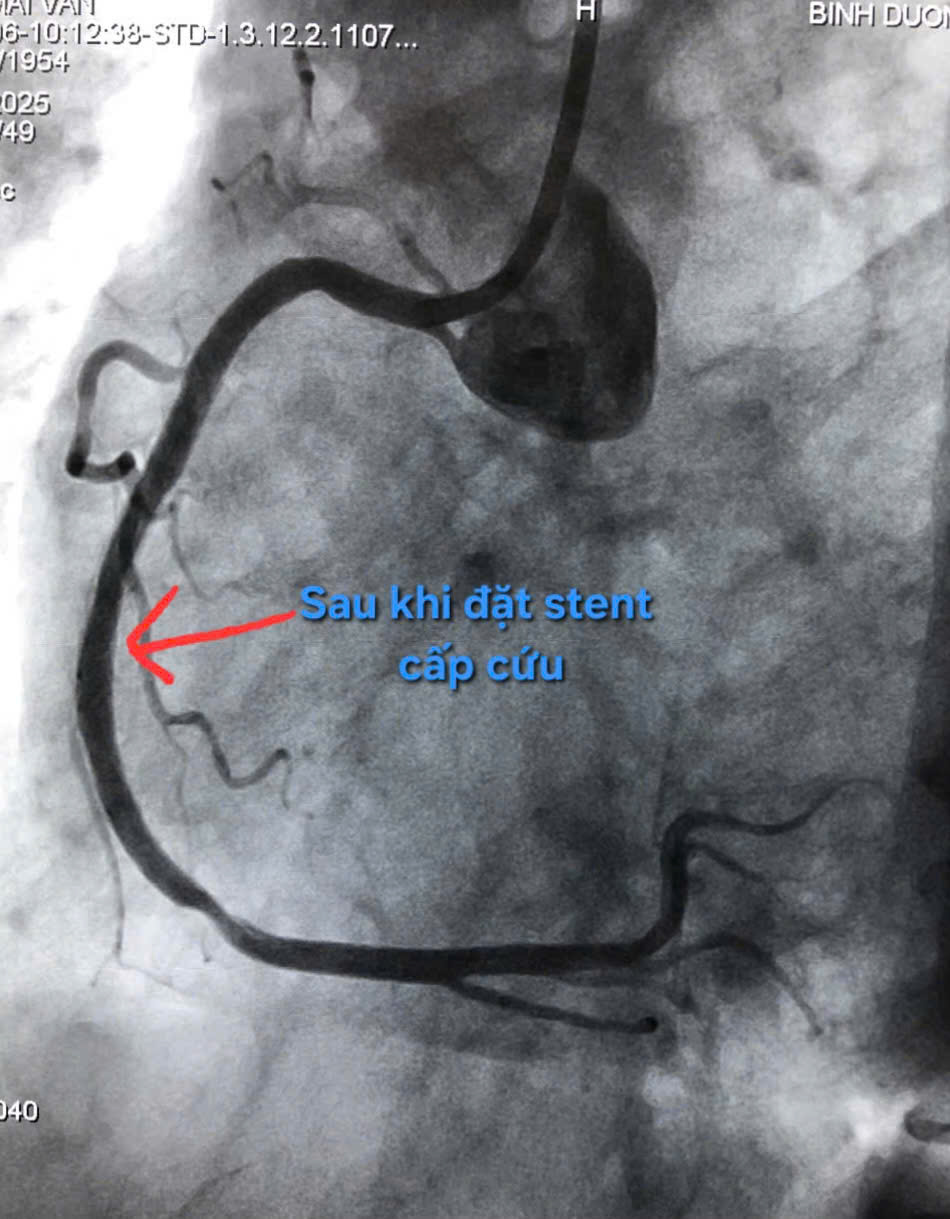

NHỒI MÁU CƠ TIM CẤP – KẺ GIẾT NGƯỜI THẦM LẶNG